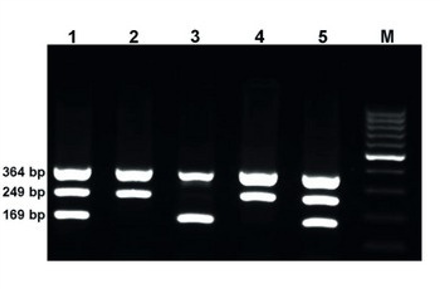

Reação em Cadeia de Polimerase (PCR) em Doenças Infecciosas

A técnica de PCR (polymerase Chain Reaction) é um método de biologia molecular de amplificação do DNA e baseia-se no processo de replicação do DNA. Através desta técnica oferecemos a pesquisa de agentes infecciosos como leishmania, HPV e microbacterias.